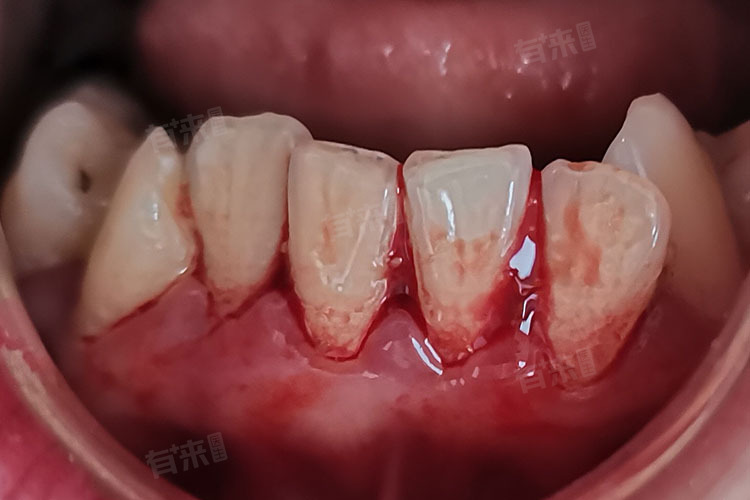

2、牙周炎:由牙龈炎进一步发展而来,除了牙龈炎症外,还伴有牙周支持组织,牙槽骨、牙周膜等破坏。牙周袋形成后,袋内细菌滋生,炎症加重,导致牙龈红肿、质地松软,极易出血。随着病情进展,牙齿可能出现松动、移位,出血症状也会更加频繁和严重。